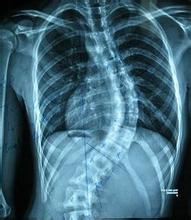

秋季来临,近在市中医院脊柱专业的门诊病人当中,强直性脊柱炎的病人又多了起来。王某,一个25岁的男性患者,之前被诊断为强直性脊柱炎已经有一年了,近半年情况良好,没有腰痛,故没有回来复查,但天气一开始转凉,他立刻又感觉到腰部开始有僵硬和疼痛感...[详细] 2015-10-29

强直性脊柱炎(osteoarthritis,OA)或称退变性关节炎、老年性关节炎、增生性关节炎。该病可能是这世界上古老且具慢性特征的疾...[详细] 2015-10-26